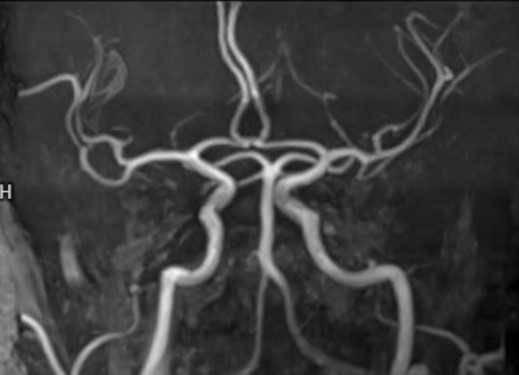

- Магнитно-резонансная ангиография. Существует две разновидности этого исследования с контрастом и без него. При этом виде исследования визуализируются сосуды головного мозга. Они похожи на веточку дерева с разветвлениями от крупных ветвей до самых мелких. Если есть изменения артерий, вен, их определяют по расширению, сужению просвета, извитости или обрыву тени при закупорке. При подозрении на кровоизлияние контраст не используют. Артериография определяет патологию артерий, венография соответственно вен. Ангиография включает полное обследование всех сосудов головы.

МР-ангиография артерий головного мозга

МР-сигнал от тока крови по ПМА, СМА и ЗМА, ВСА, основной артерии не изменен.

Асимметрия позвоночных артерий (S>D).